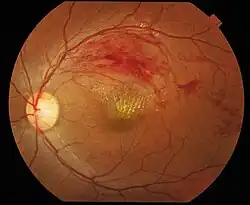

Branch retinal vein occlusion is a common retinal vascular disease of the elderly. It is caused by the occlusion of one of the branches of central retinal vein.[1]

Patients with branch retinal vein occlusion usually have a sudden onset of blurred vision or a central visual field defect. The eye examination findings of acute branch retinal vein occlusion include superficial hemorrhages, retinal edema, and often cotton-wool spots in a sector of retina drained by the affected vein. The obstructed vein is dilated and tortuous.

Retinal neovascularization occurs in 20% of cases within the first 6–12 months of occlusion and depends on the area of retinal nonperfusion. Neovascularization is more likely to occur if more than five disc diameters of nonperfusion are present and vitreous hemorrhage can ensue.[2]

The diagnosis of branch retinal vein occlusion is made clinically by finding retinal hemorrhages in the distribution of an obstructed retinal vein.